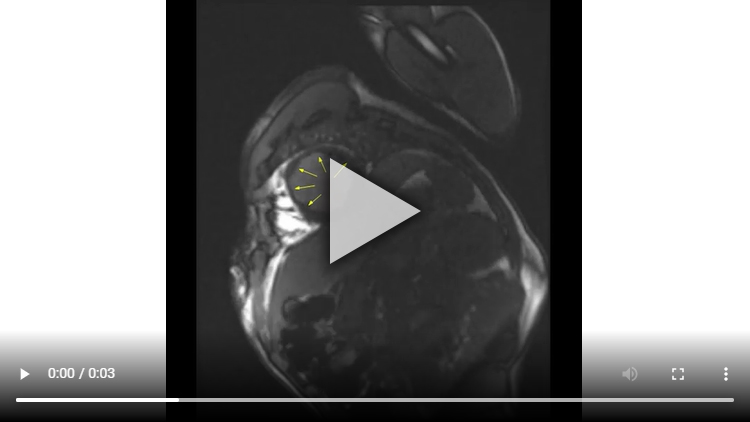

Figure 3A : Séquence de rehaussement tardif - coupe petits-axe

Figure 3B : Séquence de rehaussement tardif - coupes long-axe 4 cavités et 2 cavités

Figure 3A : Séquence de rehaussement tardif - Coupes petit-axe

Présence d’un large rehaussement tardif sous-endocardique de 8 à 9 segments sur 17 avec un réhaussement transmural (100% de transmuralité) dans la quasi-totalité des segments. Ainsi, si l’IRM cardiaque avait été réalisée à plus de 4 semaines de la phase aiguë nous aurions pu conclure avec certitude à une absence de viabilité.

Cependant, le fait d’être à seulement 2 semaines de la phase aiguë ne nous permet pas de conclure avec certitude à la non-viabilité de cet IDM

Aucun thrombus intra-VG n’est visualisé sur ces séquences de rehaussement tardif. Un thrombus serait apparu sous la forme d’une masse en hyposignal (noire) au niveau de l’apex VG par exemple.